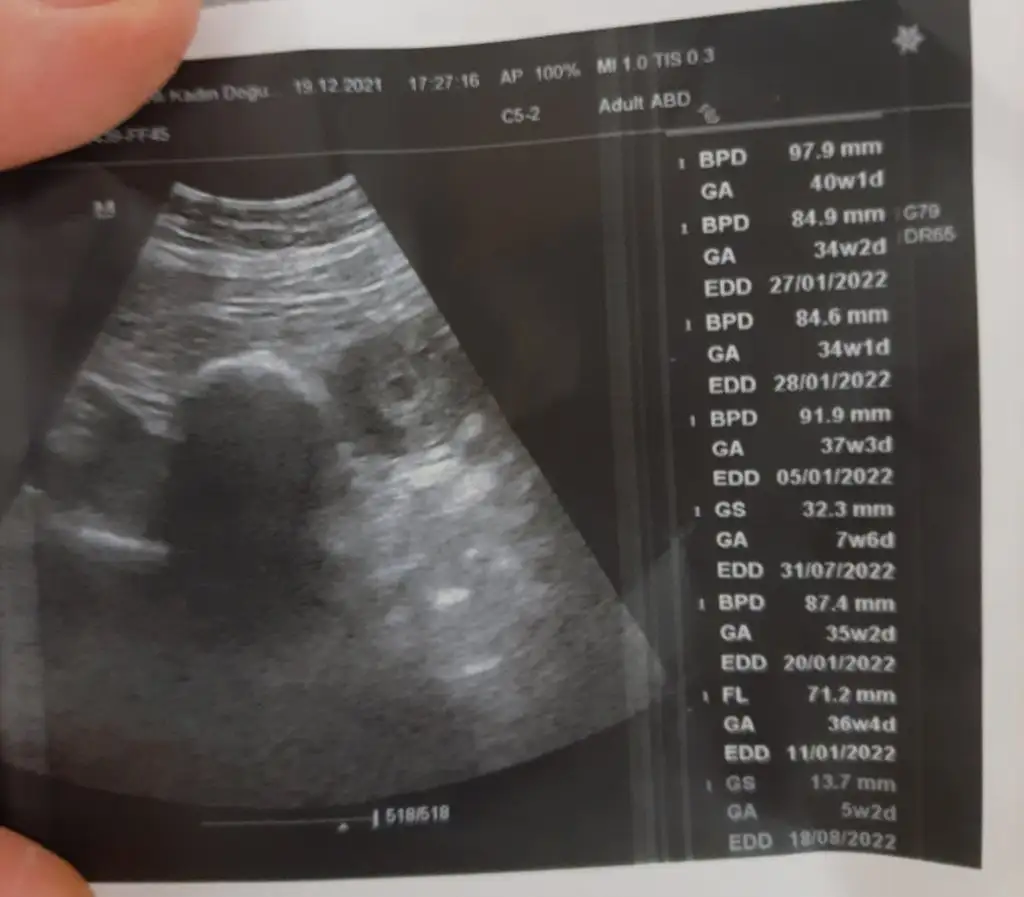

Kizlllaaarrrr :) biz 5+3 oldukTuhayy keseyi görünce bize hemen yazarsın

Yaa küçücük kesemi ordakııKizlllaaarrrr :) biz 5+3 olduk

Günaydınnn nasılsın annecikkKizlllaaarrrr :) biz 5+3 olduk